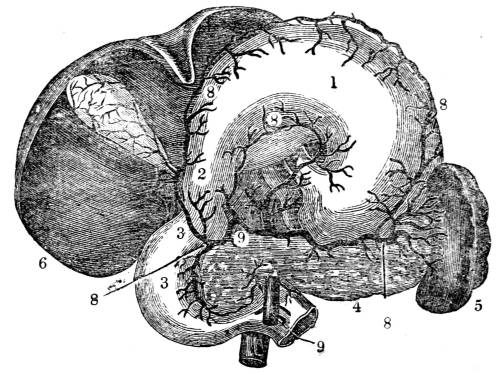

Fig. CXXIX.—

Diagram of the Apparatus of the Circulation

and Respiration in the Fish.

1. Auricle (Single) of the heart. 2. Ventricle (single) of

the heart. 3. Trunk of the branchial artery. 4. Division

of the branchial artery going to the branchiæ or gills.

5. Leaves of the branchiæ. 6. Branchial veins, which

return the blood from the branchiæ, and unite to form. 7.

the aorta, by the division of which the aërated blood is

carried out to the system.